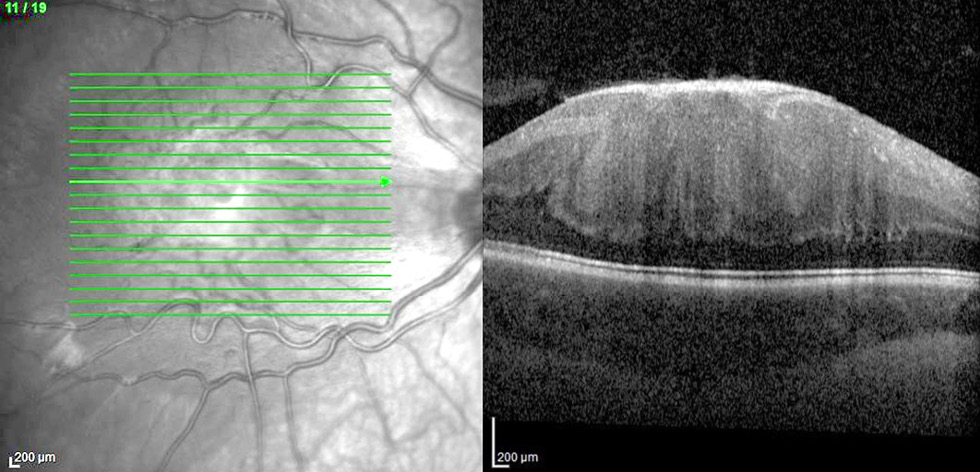

Рис. 7. Оптическая когерентная томограмма сетчатки ребёнка 4 лет с комбинированной гамартомой сетчатки и ретинального пигментного эпителия: деформация витреоретинального профиля макулярной зоны, эпиретинальная мембрана, треугольные гиперрефлективные изменения в наружном ядерном слое («зубы акулы»). Максимально корригированная острота зрения 0,03.

Fig. 7. OCT of the retina in a 4-year-old child with combined hamartoma of the retina and retinal pigment epithelium: deformation of the vitreoretinal profile in the macular zone, epiretinal membrane, triangular hyperreflective changes in the outer nuclear layer (“shark teeth”). Best corrected visual acuity 0.03.

- в четырёх глазах «зубы акулы» — треугольные гиперрефлективные изменения в наружном ядерном слое [13] (рис. 7).